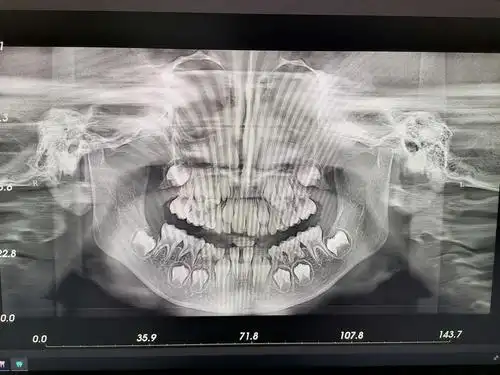

我院新引进普兰梅卡(planmeca)口腔三合一cbct,它包含了2d全景

这个是口腔全景拍片.